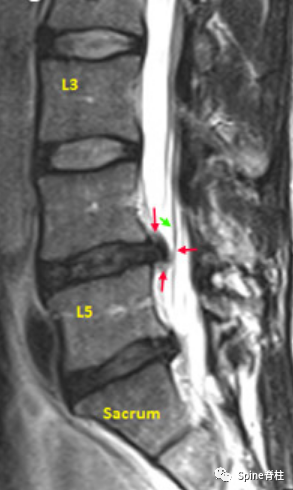

腰椎MRI旁矢状位(Para-Sagittal Region),在硬膜囊内可见走行根(红色箭头),但L5除外,它已从硬膜囊出芽(第3个红箭头)。